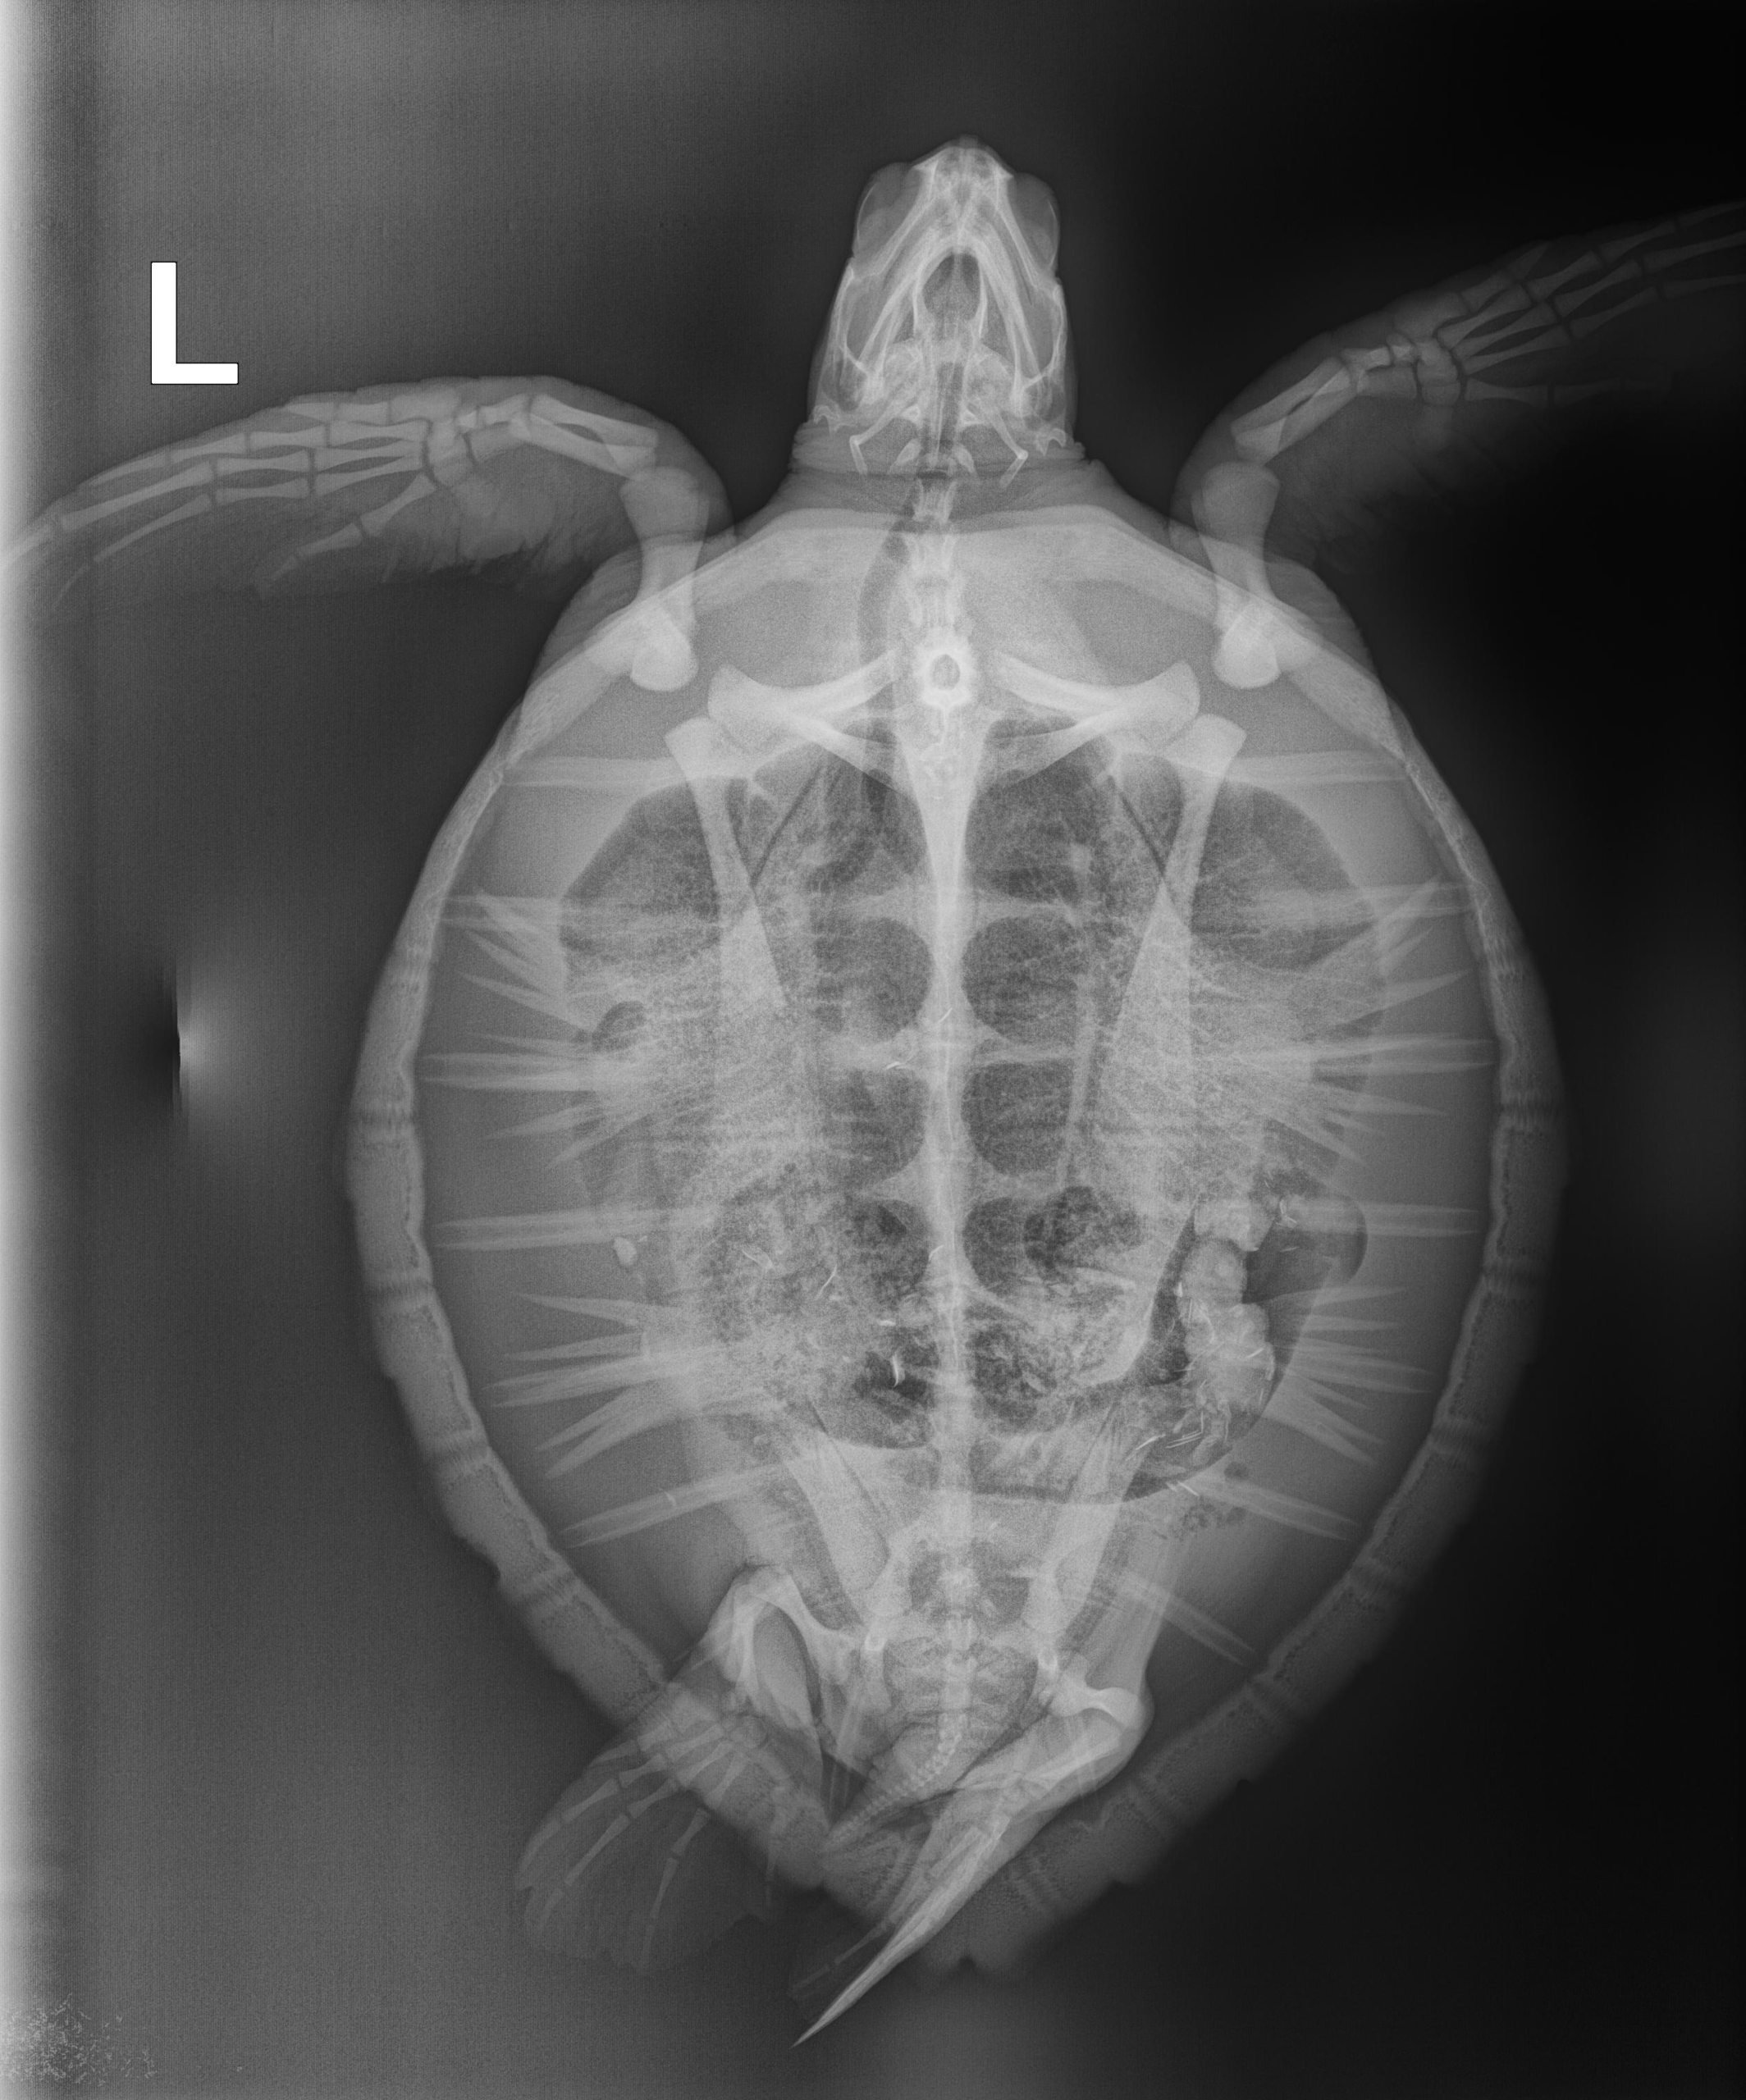

5.9 lbs. non-FP juvenile green

Entanglement wounds on LFF, minor abrasions on carapace and plastron, minor plastron bruising.